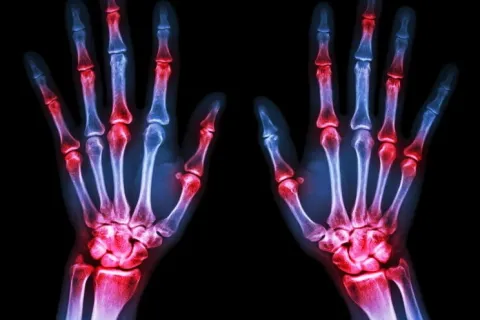

What are the most common causes of wrist pain? Wrist pain can result from various factors, including injuries,... Continue Reading

Basal Joint Arthritis Basal joint arthritis, also known as thumb arthritis or carpometacarpal (CMC) joint arthritis,... Continue Reading